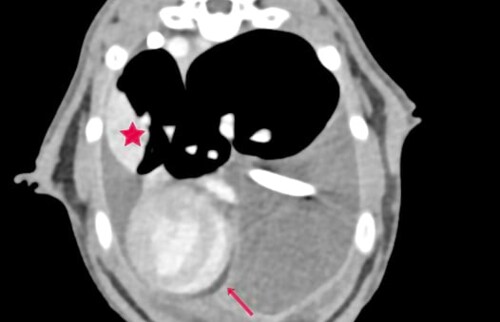

Merlin konnte nach erneuter Thora­ko­zen­tese mittels Thoraxkatheter, Therapiestart mit Rutin, Prednisolon und Buprenorphin zwei Tage lang stabil gehalten werden. Dann zeigte er erneut eine abdominal betonte Tachypnoe mit verschärftem Atem­geräusch. Sonographisch ließ sich ein bilateraler hgr Thoraxerguss sowie eine sehr verdickte und gewebige Pleura darstellen. Diese Befunde konnten in der anschlie­ßenden Computertomographie bestätigt werden, zusätzlich stellte sich der Ln. Sternalis mgr. vergrößert dar und im linken caudalen Lungenlappen war eine struk­tu­relle Veränderung zuerkennen (hypo­attenuierte, intraparenchymal, Kontrastmittel aufnehmend). (Abb. 1-3)

Perikarderguss (Pfeil), strukturelle Lungenveränderung (Stern)

Abb. 1 Perikarderguss (Pfeil), strukturelle Lungenveränderung (Stern)